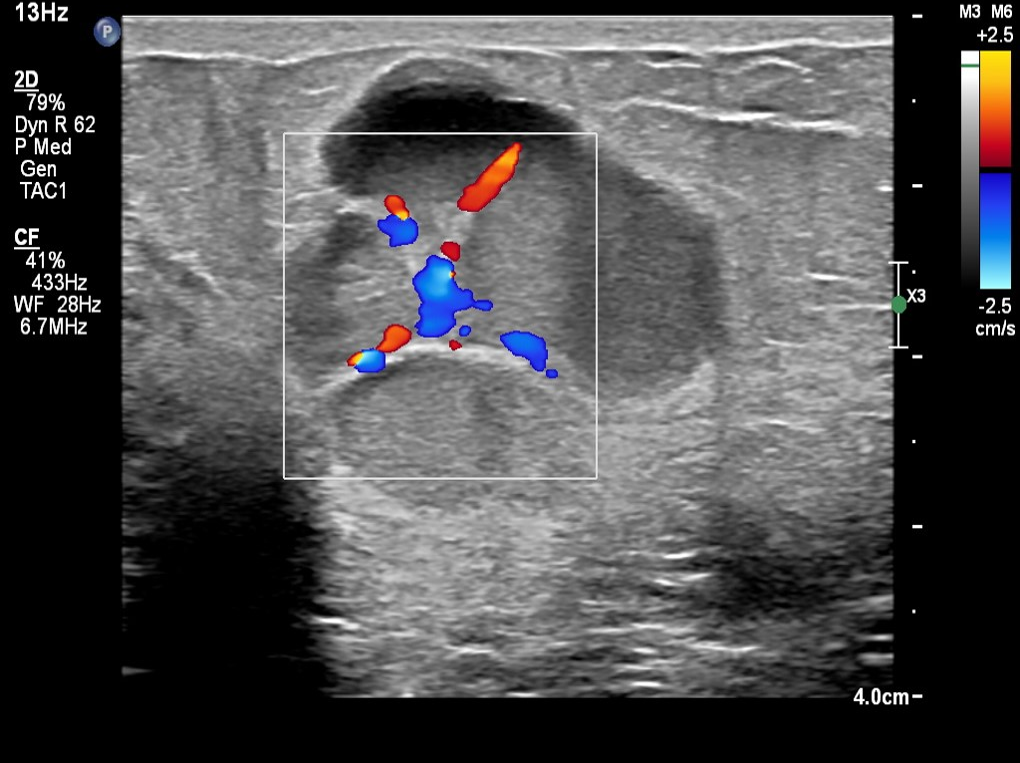

O_RADS_5

Ultrassonografia transvaginal com Doppler colorido. Observa-se massa anexial sólida, de contornos irregulares, com ecotextura heterogênea e vascularização interna ao Doppler, sem características de benignidade. Achados altamente suspeitos para malignidade, classificados como O-RADS 5.